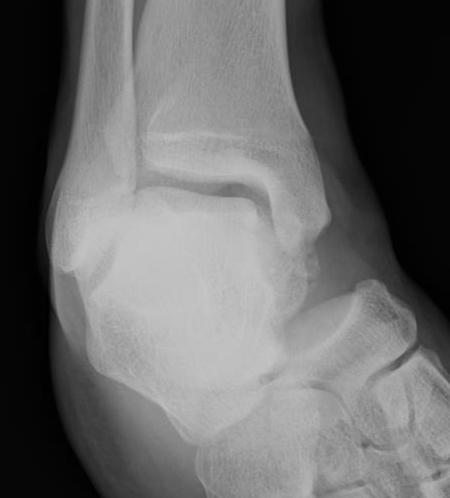

Lateral subtalar dislocation with fracture of the lateral malleolus

2. Lateral

- calcaneum dislocated laterally

- high energy trauma

- often associated with fractures

- can be difficult to reduce due to incarceration of tibialis posterior and FDL

Fibular fracture and subtalar loose bodies after lateral subtalar dislocation